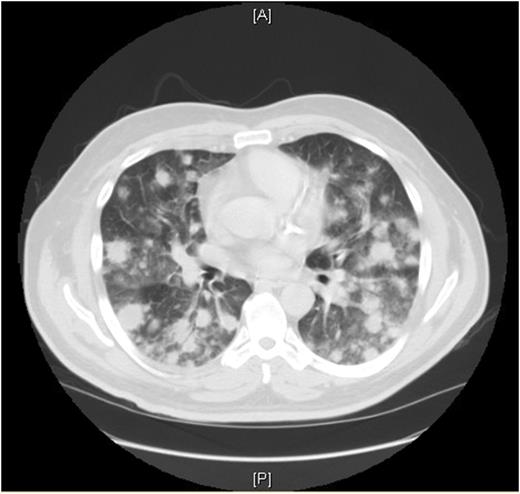

A 64-year old Caucasian gentleman presented to the Emergency Department with complaints of lethargy, weakness, progressive dyspnea on exertion, productive cough of whitish sputum and a fever of 102.5 F. His past medical history was significant for non-insulin dependent diabetes, CAD s/p stent 14 years prior, hypertension, and atrial fibrillation. He had a 14 pack year smoking history and had quit smoking 13 years prior. On review of systems, he admitted to a 5 lbs weight loss over the past 3 months, intermittent bouts of confusion and recent leg swelling. Deep venous thrombosis was excluded by his primary care physician, a week prior to admission. While in the ED, a CBC showed pancytopenia, marked by a white blood cell count of 2.7 and anemia with hemoglobin of 10.1. A CXR was performed showing bilateral pulmonary nodules; a CT scan of his chest and abdomen showed extensive pulmonary nodules and moderate splenomegaly. The patient was started on empiric antibiotics for presumed pneumonia with concerns of sepsis.